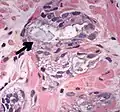

| Intraductal adenocarcinoma | 2.8%[10] | ![]() H&E and CK5/6 |

Intraductal carcinoma of the prostate with an infiltrative growth pattern may be morphologically difficult to distinguish from invasive cancer. One focus shows comedonecrosis (arrow), morphologically suggesting Gleason pattern 5 invasive carcinoma (a haematoxylin and eosin, b CK5/6)[19]

Intraductal carcinoma of the prostate with very patchy basal cells identified by immunohistochemistry. At least some of the glands lacking basal cell immunoreactivity represent intraductal rather than invasive carcinoma (a haematoxylin and eosin, b CK 5/6)[19]